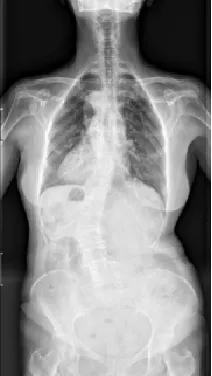

▲ 女,12岁,特发性脊柱侧凸、先天性脊柱畸形